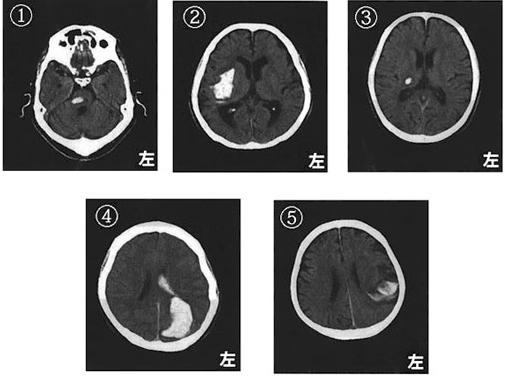

脳梗塞の発生部位によって出現する症状は異なります。この問題では、それぞれの部位における症状を正確に理解することが求められています。

右小脳半球では、右(同側)上下肢の運動失調が見られるため、この選択肢は誤りです。小脳半球の症状には、同側上下肢の運動失調や筋緊張の低下が含まれます。

右内包後脚では、左上下肢の運動麻痺が見られるため、この選択肢は正しいです。